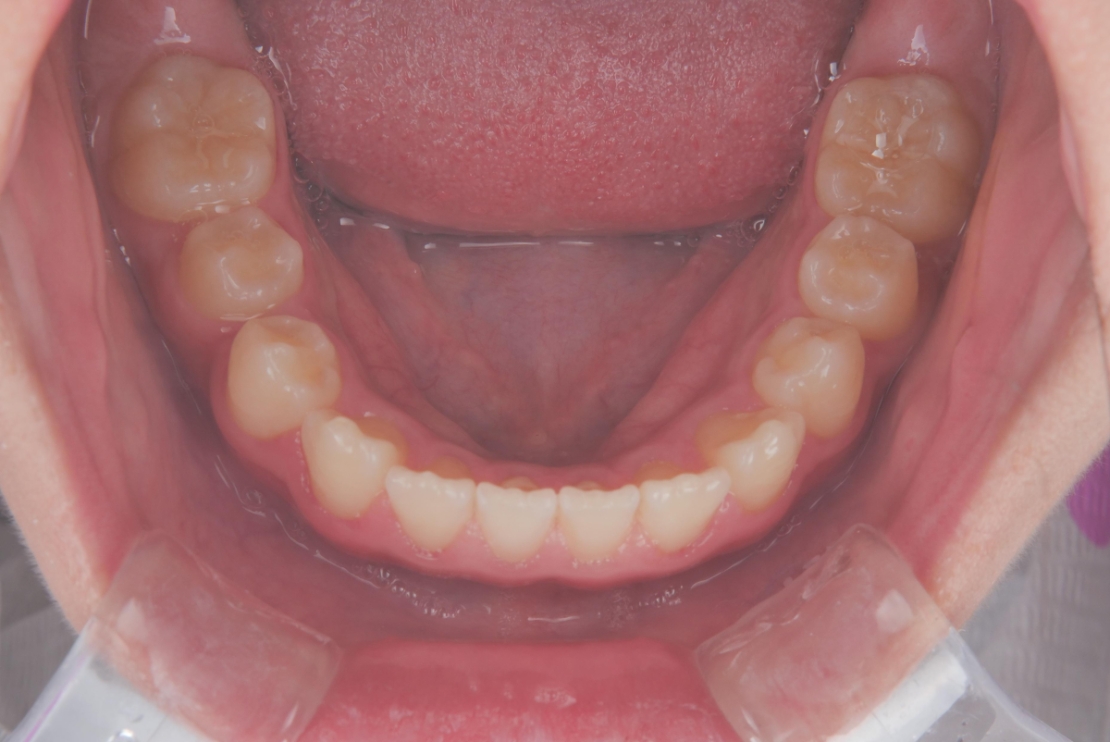

AFTER

成長を活かした治療計画のもと、まずプレオルソを1年間使用し、歯列と顎のバランスを整えました。その後、マウスピース矯正インビザライン・ファーストにて矯正治療を行い、半年間で歯並びをさらに整えています。

段階的にアプローチすることで、無理なく歯列を改善し、見た目と機能の両面を整えることができた症例です。